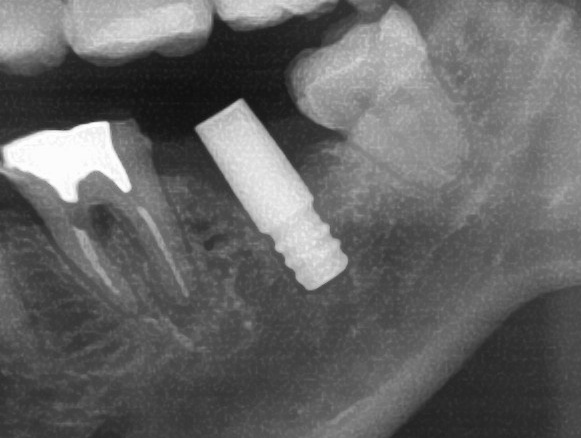

開けた穴に、専用道具を使ってネジを締めるように長さ2センチ程のインプラントを骨に埋め込んでいきます。

しっかりとインプラント埋め込まれた後は、動揺がないか、噛んだ時に当たらないかなどを確認して、最後にパノラマ写真を撮影して今回のオペは終了となりました。